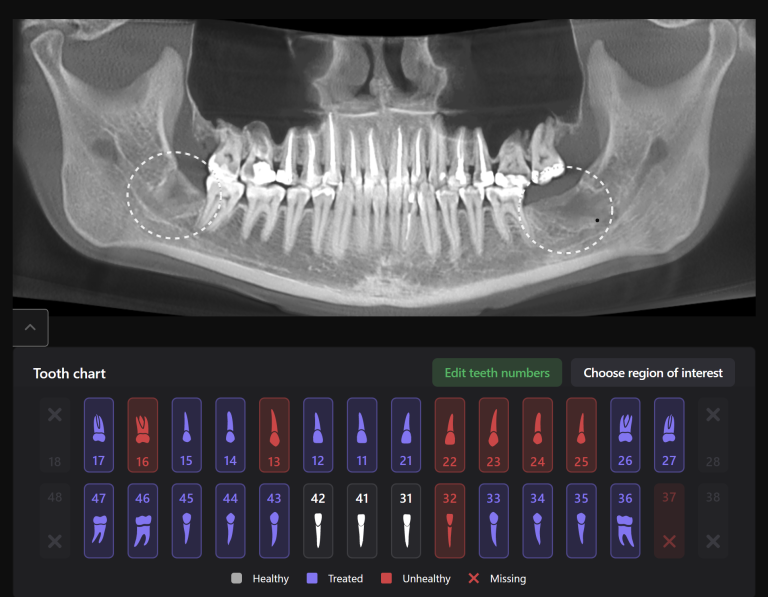

The planning of immediate implant placement using Diagnocat AI has many advantages for both the doctor and the patient. Let’s consider them using a clinical case example, in which the removal of tooth 25 (Universal 13) and subsequent implant placement were planned

In order to predict the prognosis of the tooth, data from the Diagnocat radiological report and visualization capabilities of the 3D-Viewer tool were utilized, in addition to a clinical examination